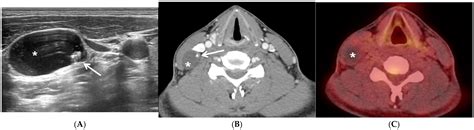

Diagnostic Approaches and Staging

Accurate diagnosis is the cornerstone of effective management. Physicians utilize a combination of imaging and molecular testing to map the extent of the disease. Because thyroid cancer can be slow-growing, imaging plays a vital role in monitoring how the cancer behaves over time.

Ultrasound Used to examine the primary tumor and suspicious lymph nodes in the neck.

PET/CT Scan Helps locate metabolic activity in areas where the cancer may have spread.